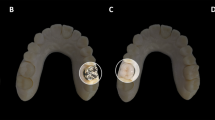

Three imaging phantoms were custom-made of three cylinder-shaped dental materials (diameter, 5.4 mm; height, 5.4 mm) arranged in an isosceles triangle (base, 58 mm; height, 39 mm; Fig. 1) and surrounded by chemically activated acrylic resin (CAAR) (VIPI, Sao Paulo, Brazil). The CAAR was poured into a mould of a cylindrical polyvinyl chloride (PVC) pipe (Tigre, Sao Paulo, Brazil) of 98 mm in internal diameter and 40 mm in height with a custom-made base of acrylic resin sealing the bottom opening, with the dental material cylinders submerged 20 mm above the lower edge of the imaging phantom. To avoid air bubble formation, the imaging phantom was kept in thermal polymerisation for 1 h at 4 bar of pressure.

All three imaging phantoms had the three cylinders made of the same dental material: dental amalgam alloy Permite (South Dental Industries, Bayswater, Australia), gutta-percha (Denstsply, York, USA) or aluminium-copper (Al-Cu) alloy Duracast MS (Dental Gaucho Marquart & Cia, Barueri, Brazil). The physical density of each cylinder was calculated based on Archimedes’ principle by using the analytical balance Discovery (Ohaus Corporation, Parsippany, USA) [13], and the outcomes for dental amalgam alloy, Al-Cu alloy and gutta-percha were, respectively, 10.6, 7.7 and 2.6 g/mL.